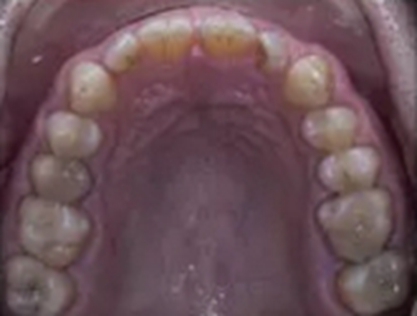

一位尋求改善微笑面容的43歲荷蘭阿爾梅勒男子通過其全科牙醫(yī)的介紹來到一家正畸醫(yī)生的私人診所,以糾正其錯合畸形并在上頜前牙區(qū)域放置6個貼面。他屬于牙形I類錯合畸形,輕度骨性III類,覆合和覆蓋減少以及前牙區(qū)存在間隙(圖1)。

在正畸咨詢前,患者定期跟隨牙齒保健師,以控制牙菌斑和牙齦炎癥,并在上頜第一磨牙和第二磨牙以及下頜右側(cè)第一磨牙和第二磨牙區(qū)域進(jìn)行潔治和根面平整。經(jīng)過6個月的牙周健康維護(hù),患者的全口出血指數(shù)低于15%,全口菌斑指數(shù)低于15%,被認(rèn)為有資格接受正畸治療。

在最初的正畸咨詢期間,拍攝了口內(nèi)和口外照片連同一張全景片(圖2),一張側(cè)位頭影片(圖3)和正畸研究模型的海藻酸鹽印模。